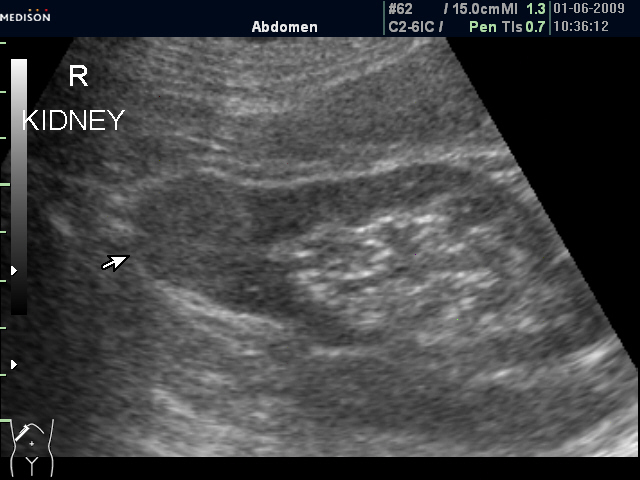

Женщина 72 лет. При УЗИ выявлены два аваскулярные образования: в нижнем полюсе правой почки и у верхнего полюса почки.

Уникальность случая в том, что эти изменения - БЕЗ ДИНАМИКИ с 2005 года.

Опухоль почки?

Опухоль почки и надпочечника.

Без допплера явно опухоль почки